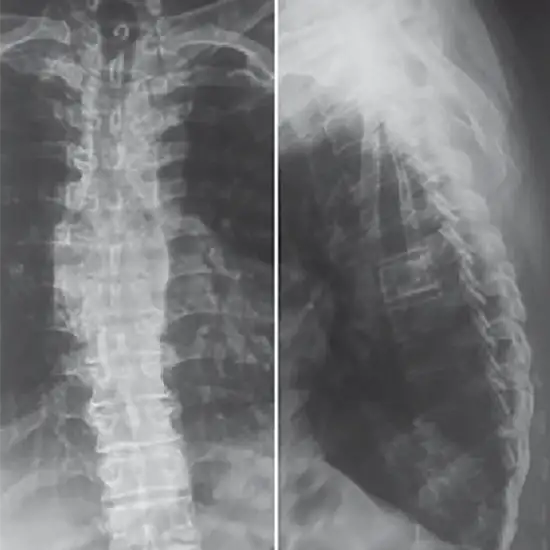

X-ray Dorsal Spine Ap View is a radiology test used to view the thoracic spine (Dorsal Spine) vertebrae(T1-T12) which form the central part of the backbone and also the intervertebral discs and the surrounding soft tissues.

The radiology test X-Ray Dorsal Spine AP View  is recommended for the diagnosis of various conditions such as

• The root cause of prolonged back pain

• Fracture or injury to the spinal bones

• If the doctor suspects the conditions such as spondylolisthesis, tumors, arthritis, osteoporosis, spinal infection, and disc degeneration.

• Abnormalities in the spinal curvature such as lordosis, kyphosis, scoliosis and birth defects, etc.